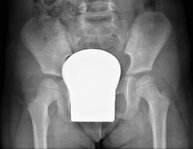

Procediment que permet, mitjançant l'ús de raigs X, i després d'injectar un contrast a l'interior de l'articulació, detectar lesions d'aquestes articulacions (cartílag, os, tendons, etc. ) segons la distribució del contrast. - RX Pelvis

Procediment que usa els raigs X a través de la qual s'obtenen imatges de la pelvis per al seu estudi, especialment dels ossos pèlvics. - RX Edat òssia